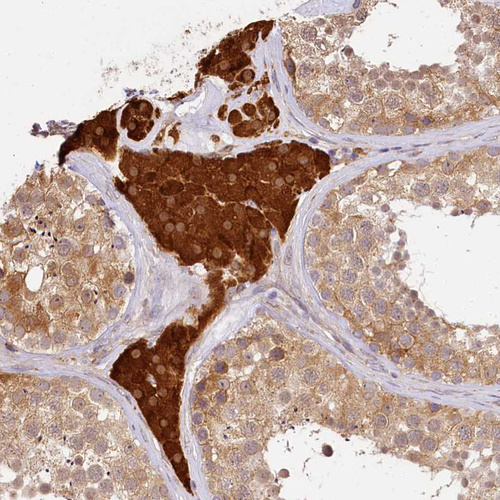

Immunohistochemical staining of human endometrium shows strong cytoplasmic positivity in glandular cells.